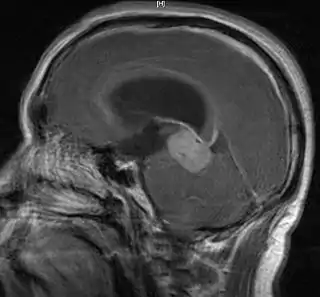

![]() Resonancia magnética del sistema nervioso central mostrando un germinoma. Véase también el corte transversal. | ||